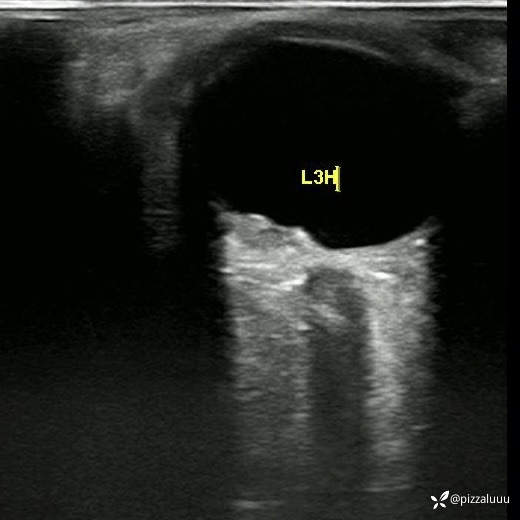

左眼轻度外斜,各位老师考虑这是什么病变?今天只做了这两项检查

玻璃体清,后极部球壁局限隆起,表面粗糙,其内回声不均